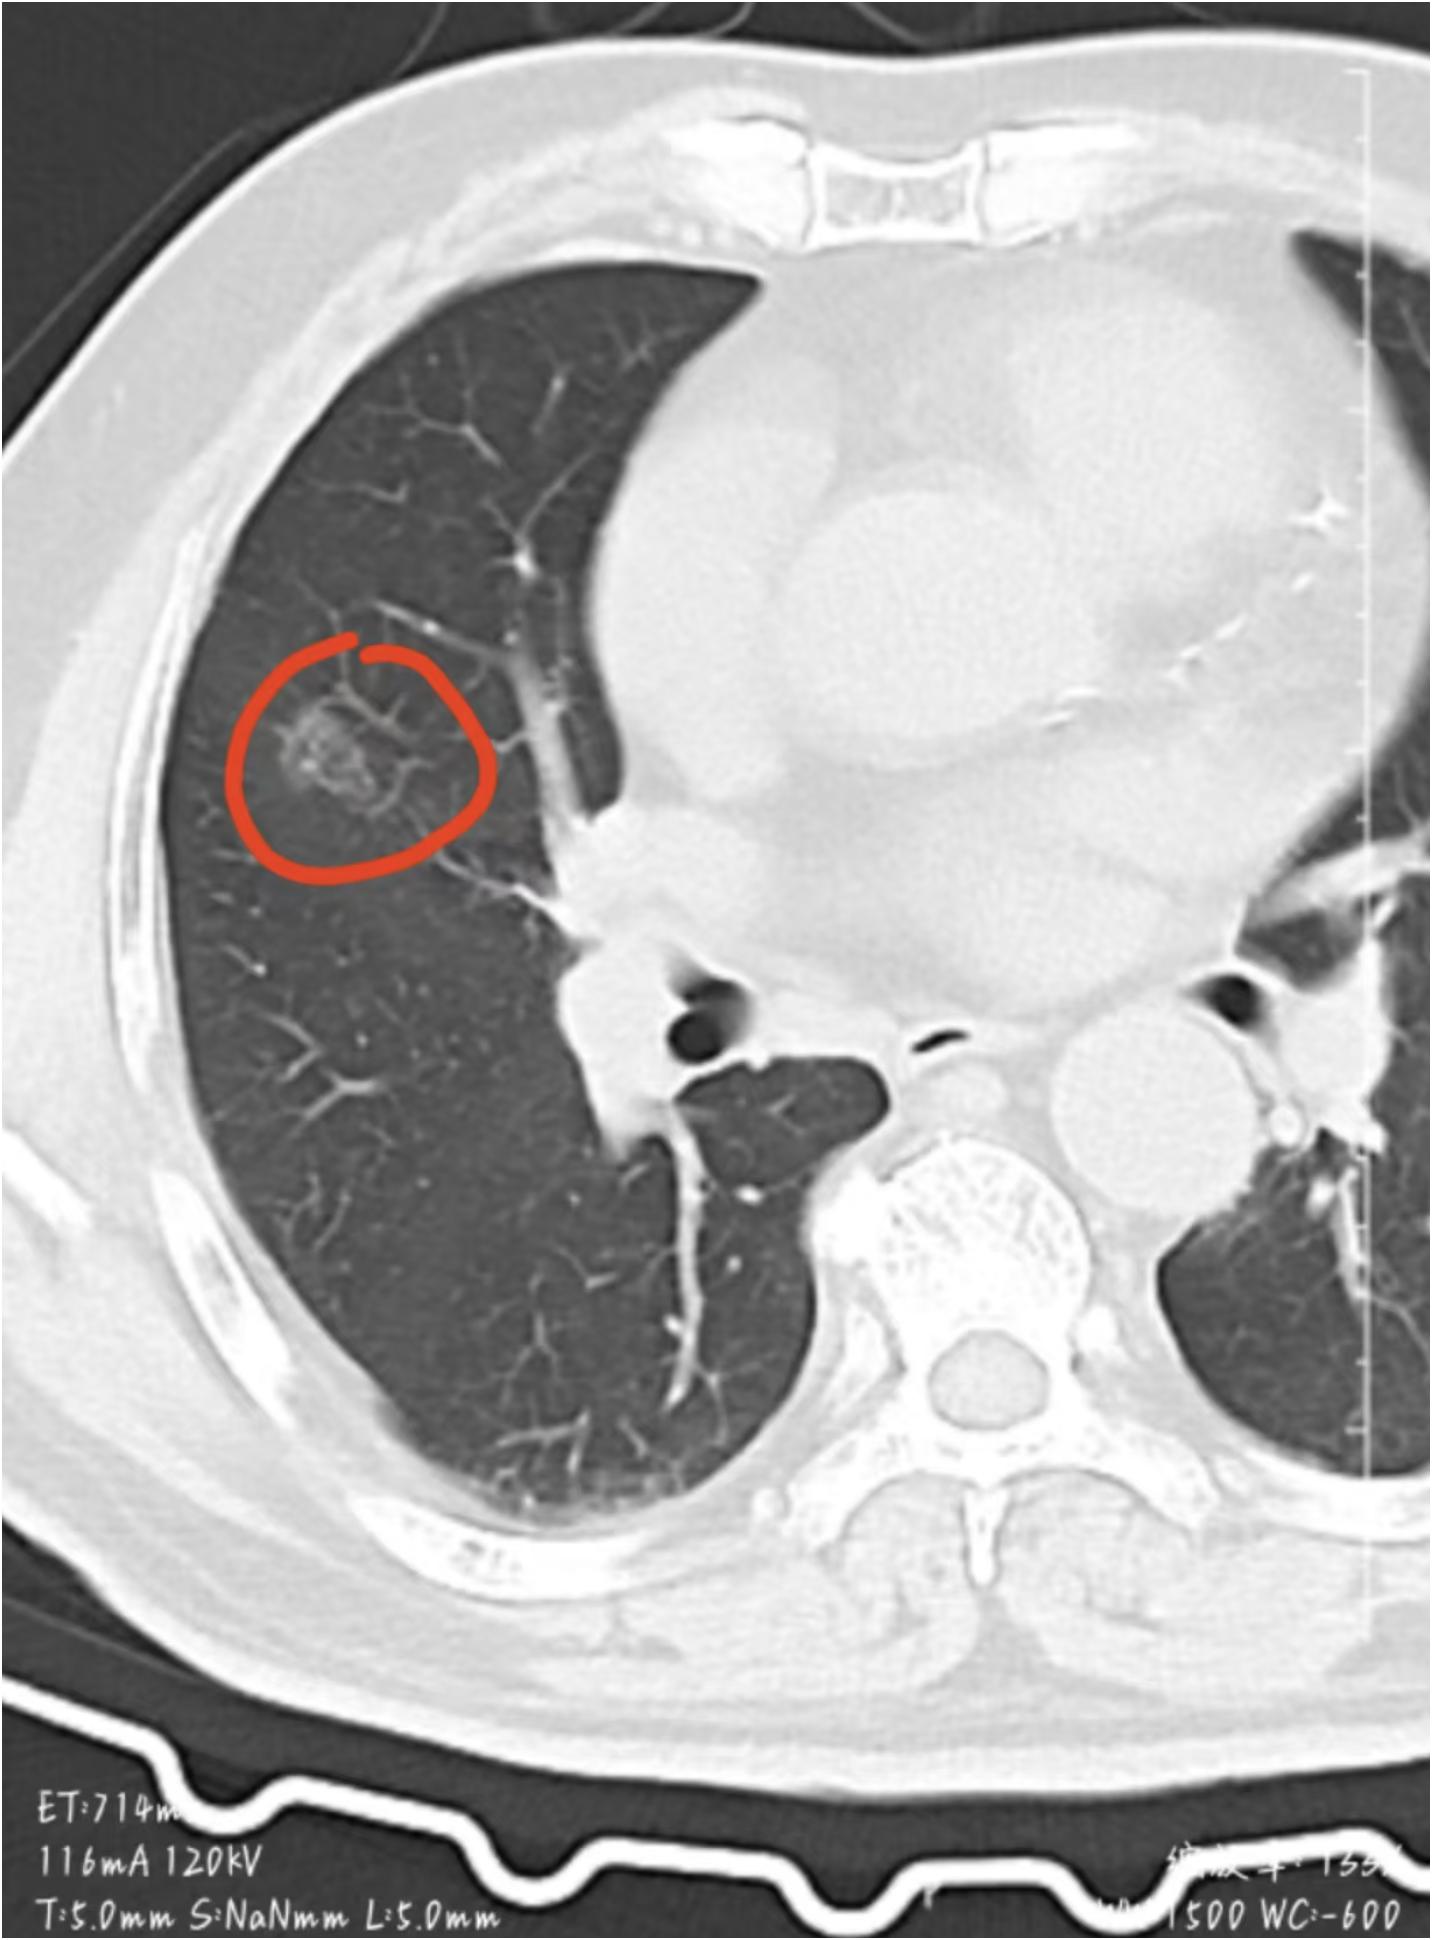

父亲最近体检查出肺结节,片子提示形态不规则、有明显恶化倾向,她没敢告诉父亲真相,自己却扛下了所有焦虑,说起这事时声音都带着颤,说 “就怕他知道后垮掉,全家都没法安心”。

细问下来,父亲的症状其实早已显现,只是自己没太当回事:平时总觉得胸闷气短,稍微走几步路就喘,胸口还偶尔有隐隐作痛的感觉;晨起总爱咳嗽,咳出来的痰是白黏的;而且总觉得身体发沉、没精神,食欲也大不如前,吃一点就腹胀